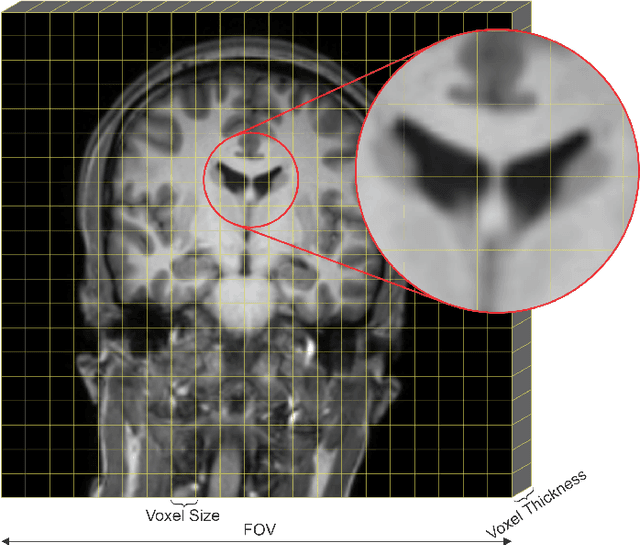

Abstract:The 2020 Multi-channel Magnetic Resonance Reconstruction (MC-MRRec) Challenge had two primary goals: 1) compare different MR image reconstruction models on a large dataset and 2) assess the generalizability of these models to datasets acquired with a different number of receiver coils (i.e., multiple channels). The challenge had two tracks: Track 01 focused on assessing models trained and tested with 12-channel data. Track 02 focused on assessing models trained with 12-channel data and tested on both 12-channel and 32-channel data. While the challenge is ongoing, here we describe the first edition of the challenge and summarise submissions received prior to 5 September 2020. Track 01 had five baseline models and received four independent submissions. Track 02 had two baseline models and received two independent submissions. This manuscript provides relevant comparative information on the current state-of-the-art of MR reconstruction and highlights the challenges of obtaining generalizable models that are required prior to clinical adoption. Both challenge tracks remain open and will provide an objective performance assessment for future submissions. Subsequent editions of the challenge are proposed to investigate new concepts and strategies, such as the integration of potentially available longitudinal information during the MR reconstruction process. An outline of the proposed second edition of the challenge is presented in this manuscript.